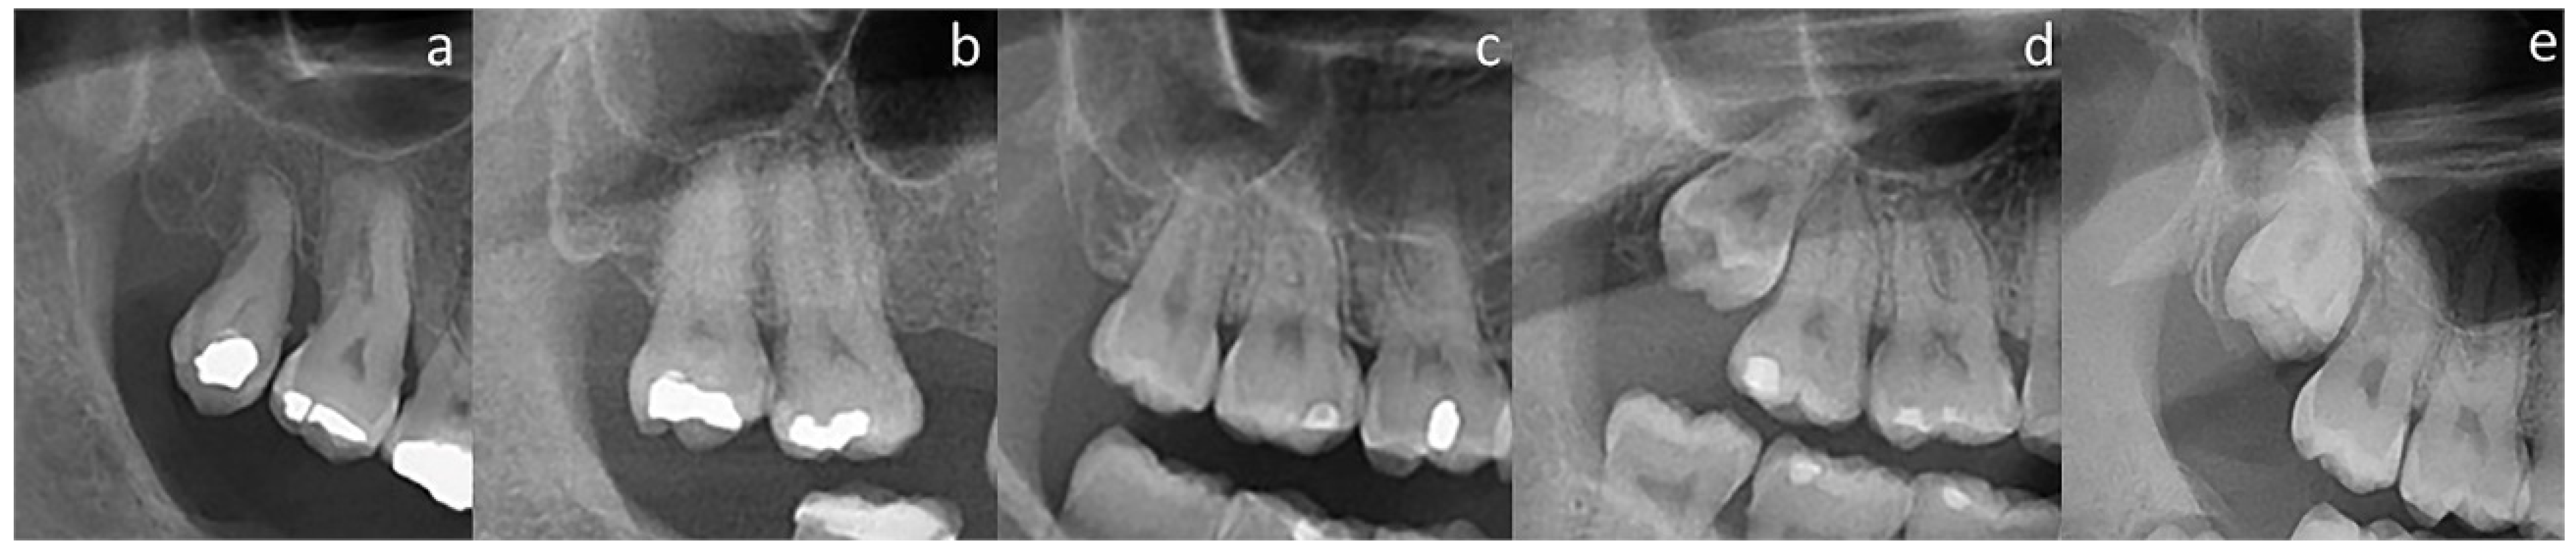

| Apices Distant from the Floor | MS Floor Touching the Roots | Presence of Alveolar Dome | Absence of Bone Covering | ||

| MS floor above the roots | 34 (75.6%) | 4 (6.1%) | 0 (0.0%) | 0 (0.0%) | 38 (18.4%) |

| Apices—MS floor in close contact | 10 (22.2%) | 28 (42.4%) | 17 (30.4%) | 8 (20.5%) | 63 (30.6%) |

| MS floor overlapping 1/3 root | 1 (2.2%) | 28 (42.4%) | 23 (41.1%) | 20 (51.3%) | 72 (35.0%) |

| MS floor overlapping 2/3 root | 0 (0.0%) | 4 (6.1%) | 8 (14.3%) | 8 (20.5%) | 20 (9.7%) |

| MS floor overlapping furcation | 0 (0.0%) | 2 (3.0%) | 8 (14.3%) | 3 (7.7%) | 13 (6.3%) |

| Total | 45 (100%) | 66 (100%) | 56 (100%) | 39 (100%) | 206 (100%) |